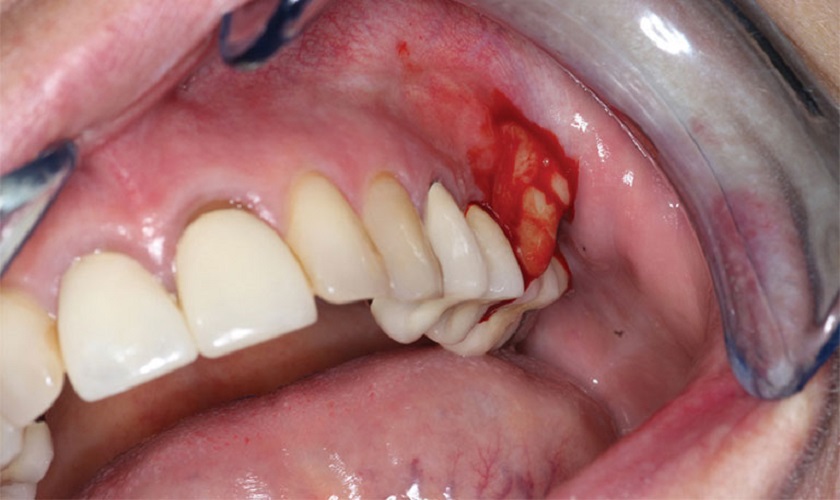

Sưng nướu răng khôn hay còn gọi là sưng lợi răng khôn là một tình trạng mô nướu xung quanh răng khôn bị viêm dẫn tới sưng, đau, gây ảnh hưởng tới khả năng ăn nhai cũng như tinh thần của khách hàng, thường xảy ra trong trường hợp răng khôn mọc kẹt do không đủ khoảng trống trên cung hàm, lúc này vi khuẩn sẽ xâm nhập vào khu vực quanh răng gây nên tình trạng nhiễm trùng, nướu xung quanh răng lúc này trở nên sưng, đỏ, đau.

Thường gặp trong những trường hợp cấp tính. Bạn có thể có sốt, mô nướu sưng đỏ, đau là khó có thể ăn nhai, khu vực quanh răng khôn có thể tiết ra dịch rỉ viêm màu trắng sữa.

Răng khôn mọc ngầm

Nếu nướu của khách hàng co biểu hiện nhiễm trùng nặng, có mủ trắng, lúc này bác sĩ sẽ tiến hàng làm sạch vùng quang răng, dùng giảm đau, kháng sinh để hạn chế đau.Cắt lợi trùm răng khôn: Nếu trường hợp mô nướu sưng nhiều trùm kín trên thân răng khôn thì bác sĩ sẽ tiến hành phẫu thuật cắt lợi trùm, sau đó sẽ kê đơn thuốc giảm đau kháng sinh cho khách hàng để răng khôn được phát triển bình thường.

Đối với những trường hợp răng khôn bị kẹt, không đủ khoảng trống để mọc trên cung hàm. Lúc này, việc nhổ răng khôn là một chỉ định bắt buộc. Khách hàng sẽ được các bác sĩ phẫu thuật để loại bỏ răng khôn.